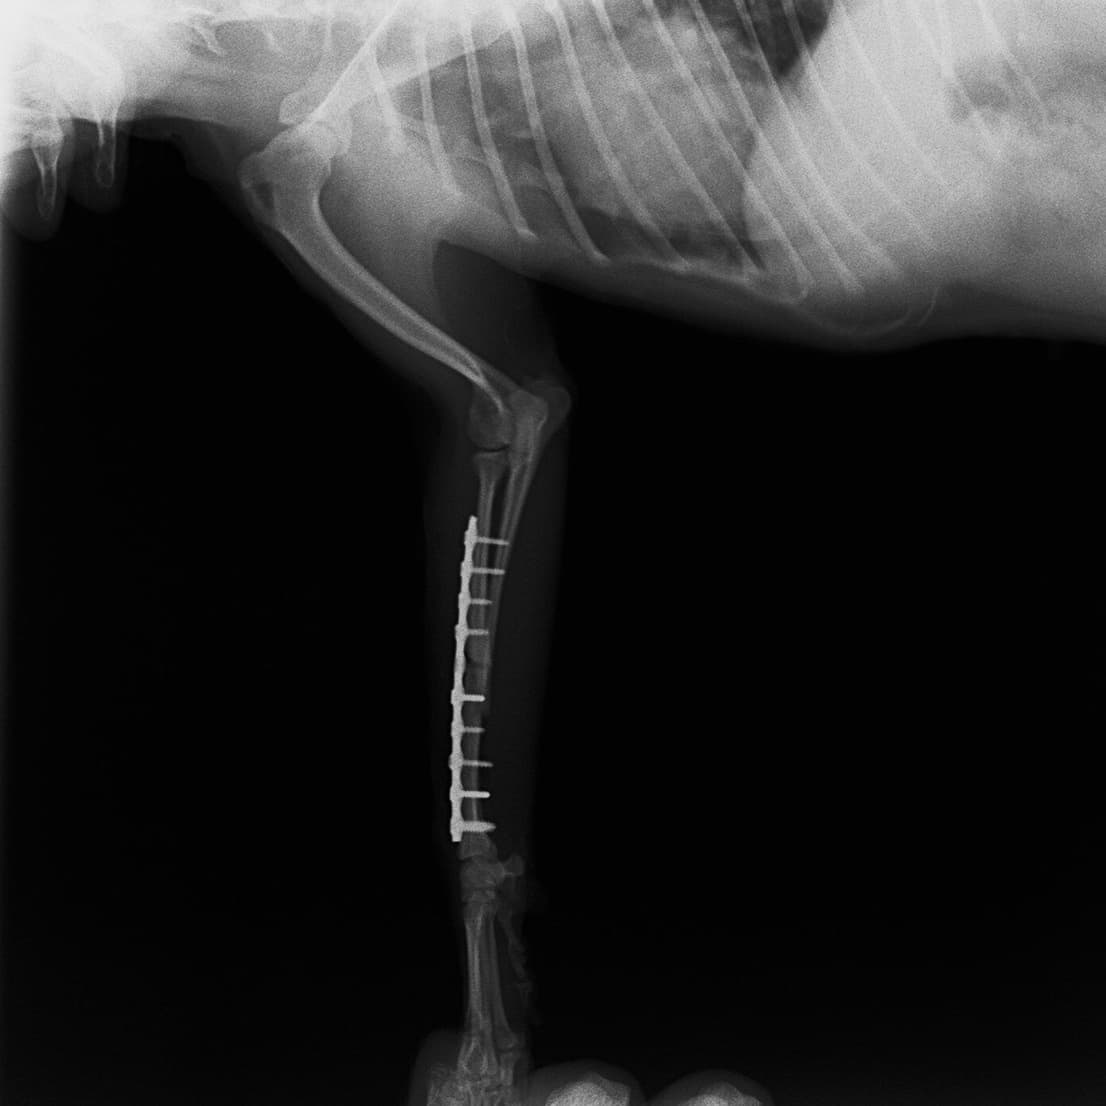

症例:交通事故による椎体脱臼

柴犬:9歳、避妊雌

交通事故直後、胸腰部に激しい疼痛、両後肢に完全麻痺を認め、シェフシェリントン徴候を呈していました。レントゲン検査において、第11-12胸椎間の脱臼が認められました。

脊髄の減圧、脊柱管の再構築・安定化を目的に、片側椎弓切除術およびMatrixMANDIBLE Plateによる椎体固定を実施しました。

隣接椎体を架橋するようにプレートを設置しました。

術後レントゲン写真